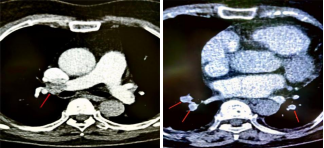

面对突发情况,医院第一时间启动MDT(多学科联合会诊)方案和DVT(下肢深静脉血栓)学组运行机制,心内科、呼吸科、ICU、外科、影像科及超声科组成的专家组紧急到达现场展开救治。期间,综合病人临床表现及各项影像、实验室检查,初步考虑肺动脉栓塞;为进一步明确诊断,行肺动脉CTA,检查结果显示:右肺动脉主干、下叶分支及左肺下叶分支血管内见充盈缺损改变,随时有生病危险。

时间就是生命,经与病人家属充分沟通后,介入组医务人员紧急行肺动脉介入手术进行治疗。术中,肺动脉造影证实右肺动脉主干及双肺动脉分支血栓形成,先后给予导管碎栓、溶栓;复造影肺动脉血流较前明显通畅,患者生命体征平稳,呼吸症状显著改善,氧饱和度稳定在95%以上。术后,患者转入心内科普通病房,进一步后续治疗。